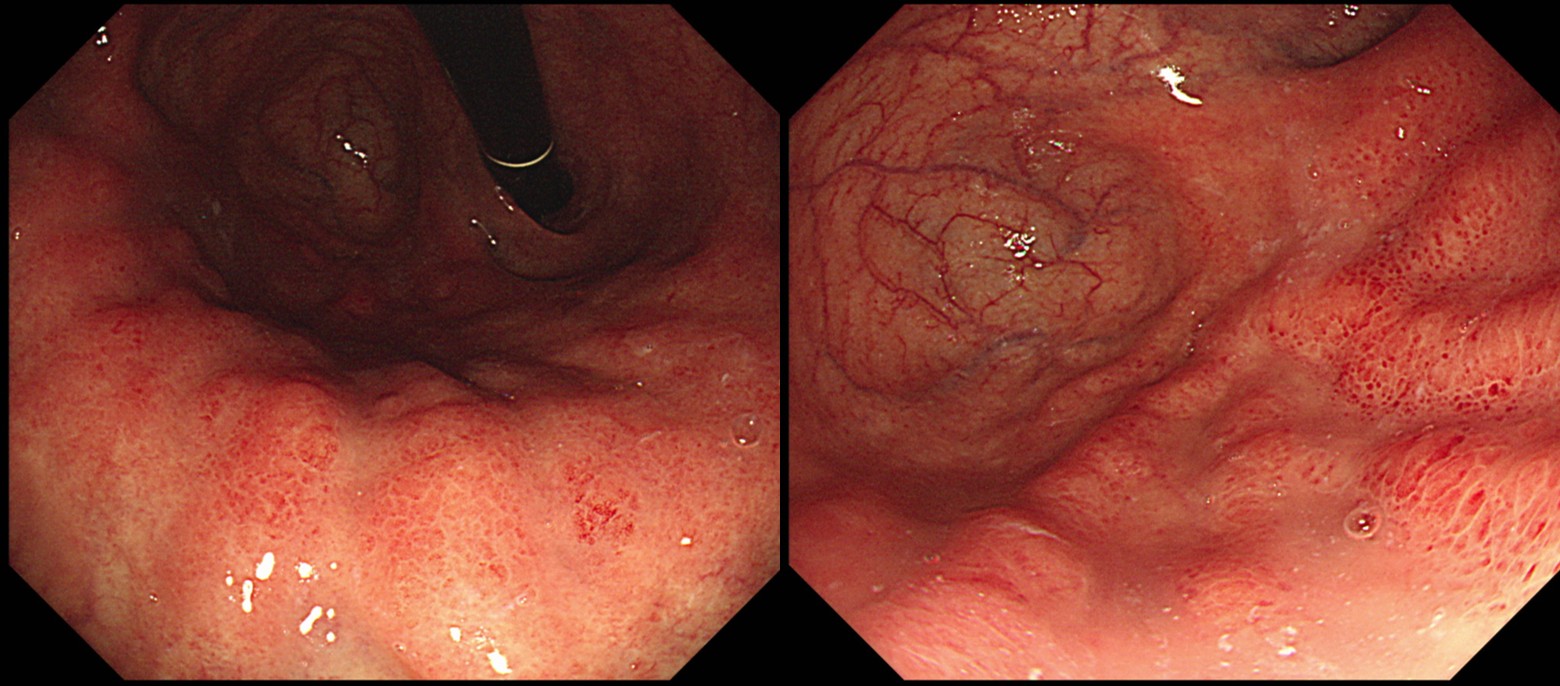

°ËÁø ³»½Ã°æ¿¡¼­ À§ÀúºÎÀÇ ÀÛÀº °áÀýÀÌ ¹ß°ßµÇ¾ú°í(±×¸² A,B), Á¶Á÷°Ë»ç¿¡¼­ monotonous atypical cell proliferation, favor neuroendocrine tumor·Î ÀǷڵǾú°í ¿ÜºÎ ½½¶óÀ̵å ÀçÆÇµ¶Àº well-differentiated neuroendocrine tumor (NET)¿´´Ù. CT¿¡¼­´Â À§ÀÇ º´¼Ò³ª ÀüÀÌ ¼Ò°ßÀº °üÂûµÇÁö ¾Ê¾Ò´Ù. Serum gastrinÀº 404pg/ml·Î ³ô¾ÆÁ® ÀÖ¾ú´Ù. Lindi ºÐ·ù Á¦1Çü À¯¾ÏÁ¾À¸·Î Ưº°ÇÑ Ä¡·á ¾øÀÌ °æ°ú°üÂûÀ» ÇÏ¿´´Ù.

13³â ÈÄ ÃßÀû³»½Ã°æ¿¡¼­ µ¿ÀÏÇÑ ºÎÀ§ÀÇ °áÀýÀÌ ÀǹÌÀÖ´Â º¯È­´Â ¾ø¾úÀ¸¸ç (±×¸² C,D) Á¶Á÷°Ë»ç´Â well differentiated neuroendocrine tumor (carcinoid) (G1)·Î º¸°íµÇ¾ú´Ù (±×¸² E).

NET ¹ß°ß 13³â µ¿¾È º¯È­°¡ ¾ø¾ú°í Á¶Á÷°Ë»ç¿¡¼­µµ grade 1À¸·Î ³ª¿Ô´Ù. ³»½Ã°æ¿¡¼­ À§Ã¼ºÎ¿Í À§ÀúºÎ Á¡¸·ÀÇ À§ÃàÀº ÇöÀúÇÏ¿´À¸³ª (±×¸² C), ÀüÁ¤ºÎ Á¡¸·¿¡¼­´Â À§ÃàÀÌ °üÂûµÇÁö ¾Ê¾Ò´Ù (±×¸² D). ³»½Ã°æ¿¡¼­ reverse atrophy ¼Ò°ßÀÌ ÇöÀúÇÏ¿´°í ÃÖ±Ù ¿ì¸®³ª¶ó¿¡¼­ ÀÚ°¡¸é¿ªÀ§¿°ÀÌ ÀûÁö ¾Ê°Ô Áø´ÜµÇ°í ÀÖÀ¸¹Ç·Î ȯÀÚ¿¡°Ô ¼³¸íÇÑ ÈÄ °ü·Ã °Ë»ç¸¦ ÇÏ¿´´Ù. Anti-parietal cell antibody ¾ç¼º, Helicobacter pylori antibody À½¼º, pepsinogen-1 9.9ng/ml, pepsinogen-2 12.4ng/ml, pepsinogen 1/2 ration 0.8, gastrin 400pg/mlÀ̾ú´Ù. ÀÚ°¡¸é¿ªÀ§¿°°ú µ¿¹ÝµÈ NET·Î Áø´ÜÇÏ¿´´Ù.